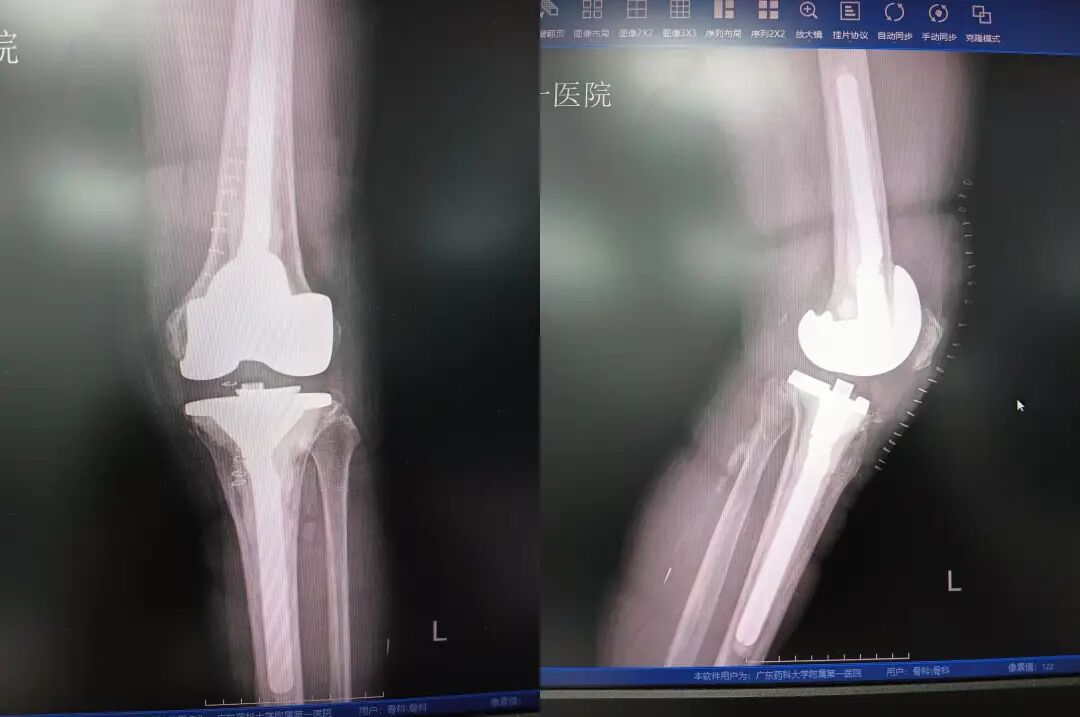

术后患者恢复正常膝关节关节状态。